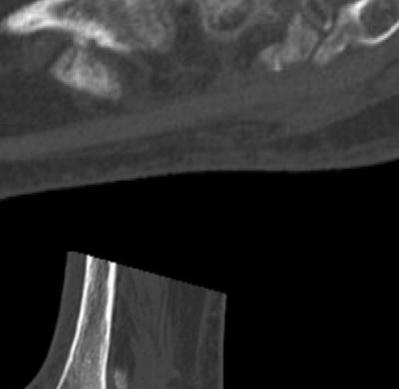

921 Charcot Neuroarthropathy of the Foot and Ankle in the Acute Setting: An Illustrative Case Report and Targeted Review

Kian Bagheri, Albert T. Anastasio, Alexandra Krez, Lauren Siewny, Samuel B. Adams

Duringthestudyperiodatotalof21participants comprising19residents(sixpostgraduateyear[PGY]1,